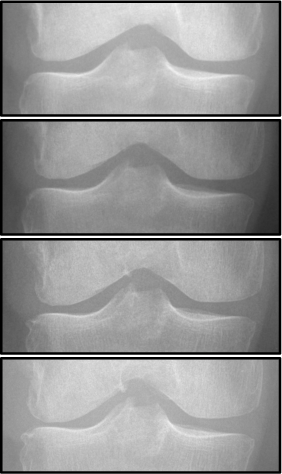

Refer to caption

(d)

Figure 5: Examples of attention maps for progression cases and the corresponding visualization of progression derived using follow-up images from MOST datasets. Here, subplots (a) and (c) show the attention maps derived using a GradCAM approach. Subplots (b) and (d) show the joint-space areas from all the follow-up images (baseline to 84 months). Here, the subplot (b) corresponds to the attention map a) and the subplot (d) corresponds to the attention map (c).

While machine learning-based approaches yield stronger prediction than conventional statistical models, (e.g. LR), they are less transparent, which can lead to lack of trust from clinicians. To address this drawback, various methods have been developed to explain the decisions of ”black-box systems” [24, 26, 27]. As such, we utilized the GradCAM approach [24] that allowed us generating an attention map, in order to highlight the zones where the CNN has paid its attention. While being attractive, this approach can also lead to wrong interpretations, i.e. there is no theoretical guarantee that the neural network identifies causal relationships between image features and the output variable. Therefore, a thorough analysis of the attention maps is required to assess the significance of certain features and anatomical zones picked-up by the model. Such analysis, however, could enable new possibilities for investigation of the visual features. For example, we observed interesting associations in the GradCAM-generated attention maps (Figure 5), some of which are not captured by KL grading. As such, tibial spines (previously associated with OA progression [28]) were highlighted in multiple attention maps. These associations, however, do not hold for all the progressors.